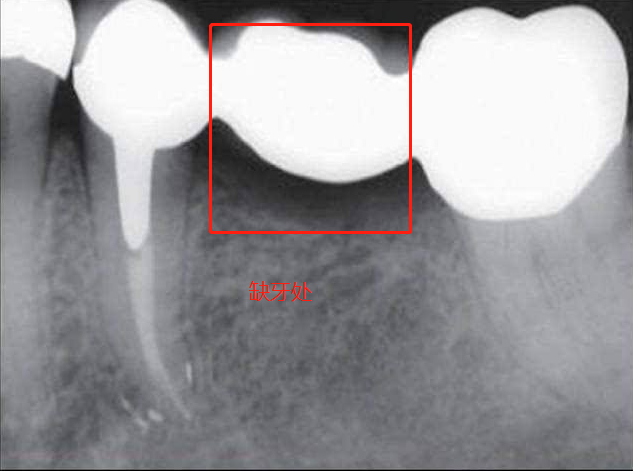

固定橋修復

固定橋的結構就像是一座橋梁,缺牙間隙部分是橋梁的身體,缺牙間隙兩邊的健康牙齒(牙基)是兩個橋頭(見上圖)。在牙齒修復完成之后,缺失的牙齒就和它前后兩顆牙齒連接成了一個整體。